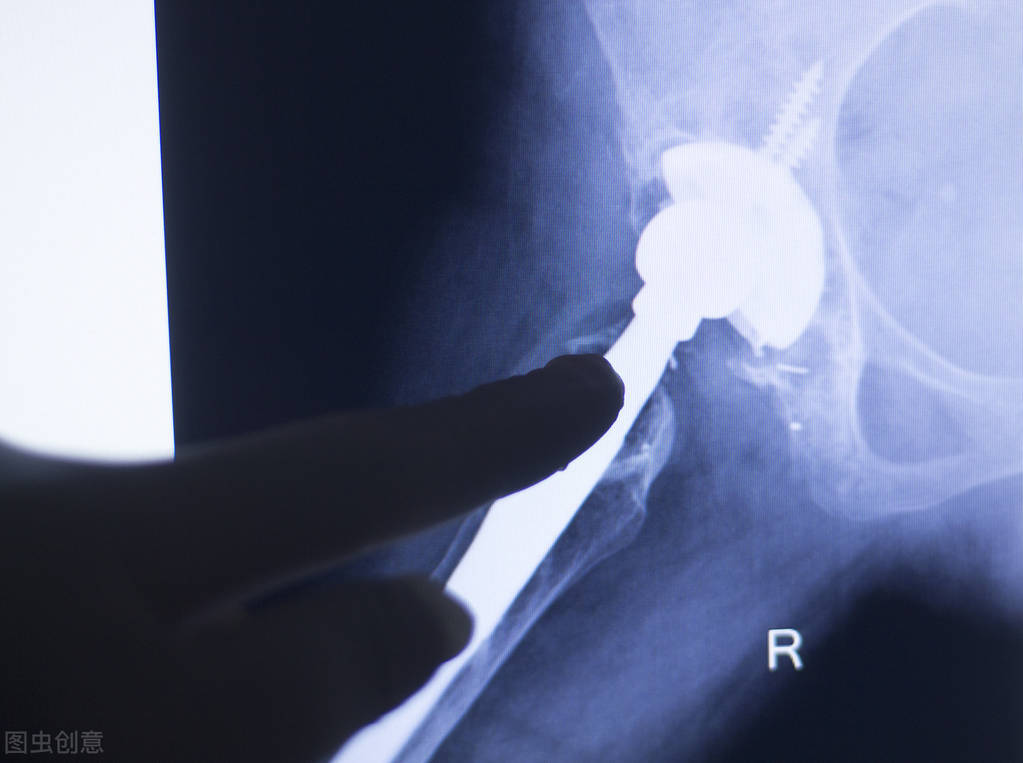

类风湿病是非常常见的一种病情,在很多患者经过多方治疗之后,还是没有见到任何的效果,特别是很多患者出现关节疼痛,手指肿胀,这个时候患者会经过相当多的治疗,但是渐渐会对治疗失去信心,其实我们对于这种疾病了解得不够充分,采取具体的治疗措施,可以有效的改善我们身体的病情。